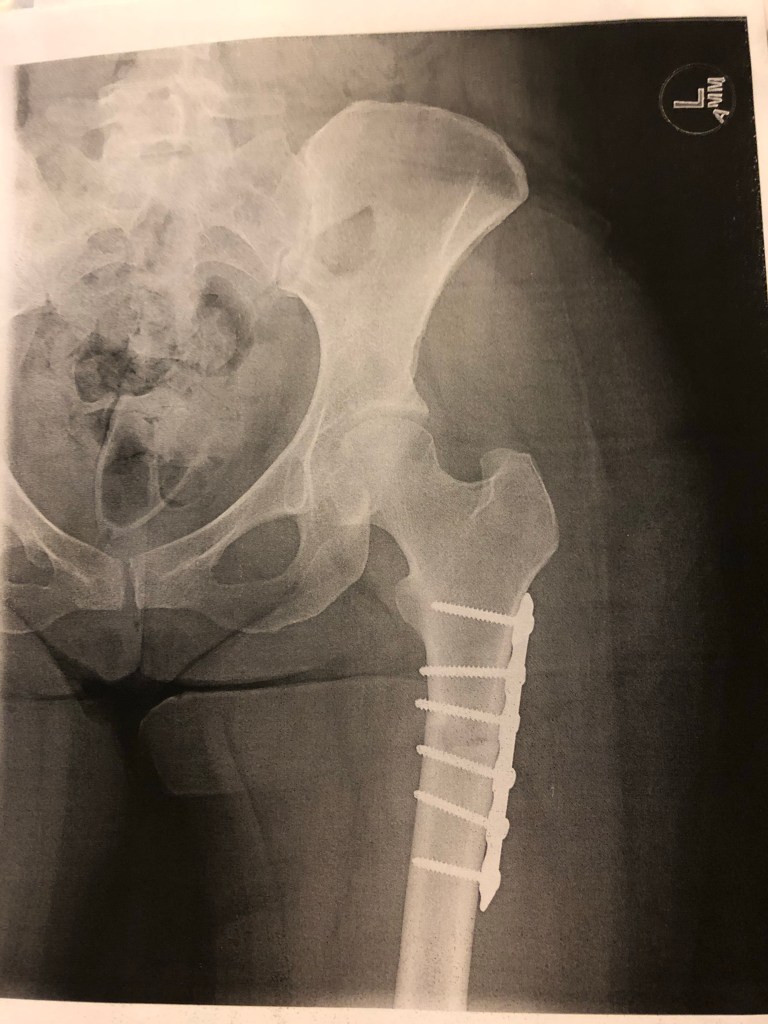

My left femur plate. The break is between the third and fourth screws.

I’m typing this while I’m lying in bed, my left leg in a continuous passive motion machine, and my left femur cut cleanly in half, the bone held together by a metal plate and six screws from the femoral osteotomy I had at the Cleveland Clinic Dec. 1. In November 2019, I had the same procedure on my right femur. Five other surgeries since 2015 addressed bony overgrowth in the joints, torn labrums, damaged cartilage and more.